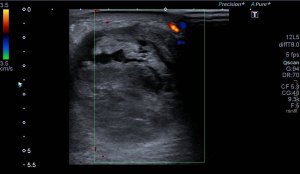

Lo que ves en estas imágenes que te voy a poner aquí son los hallazgos ecográficosque he podido visualizar hoy. Los voy a complementar con la correlación con las imágenes de TAC. En este caso específico con la eco solo se pudo corroborar los hallazgos del escáner, que a nivel anatómico arroja un mejor desarrollo de la anatomía regional implicada en el proceso.

6En el corte longitudinal de la imagen 1 ya se ve una vaso perimetrado por una imagen hiperecogénica, no compresible a la presión con la sonda convexa. En la imagen 2 con la sonda lineal se observa el enrejado habitual de los stents, que en otras ocasiones ya hemos comentado en otro post en localización distinta.